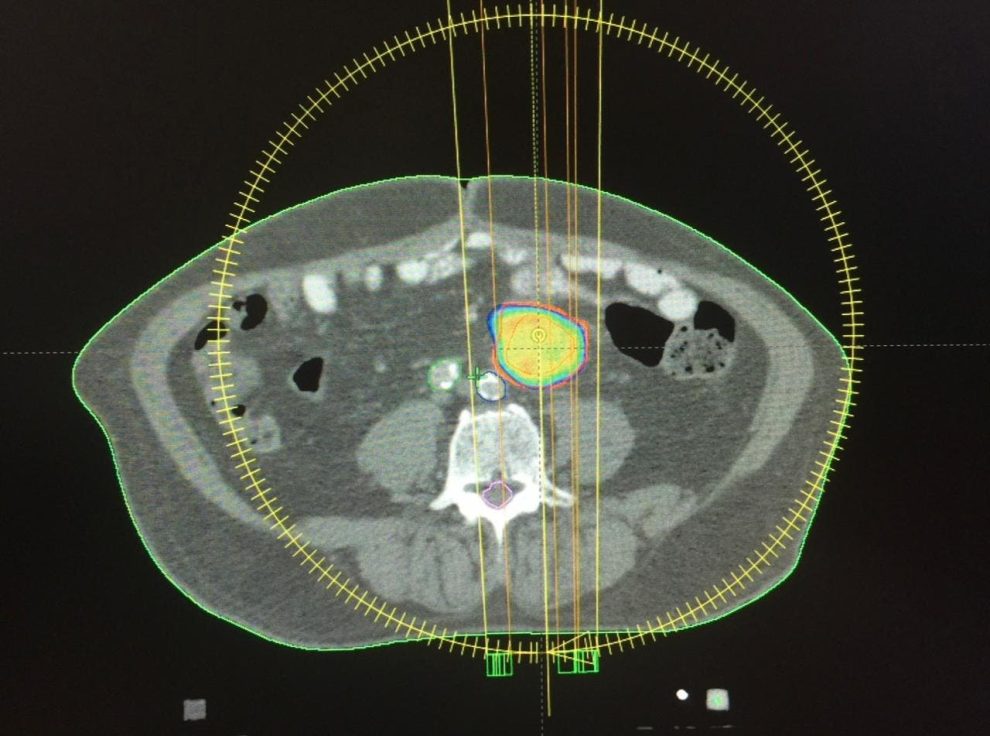

En 2015, los expertos de SHOFM practicaron con éxito la primera técnica de radiocirugía extracraneal, utilizando tecnología de corte avanzada en el Centro Oncológico. La práctica se realizó en un paciente con metástasis primaria en ganglios linfáticos, mediante PET-CT y tomografía computarizada de doble contraste de abdomen y pelvis, fusionando las dos imágenes y posterior verificación antes del tratamiento, utilizando imágenes de tomografía computarizada del objetivo a tratar. .